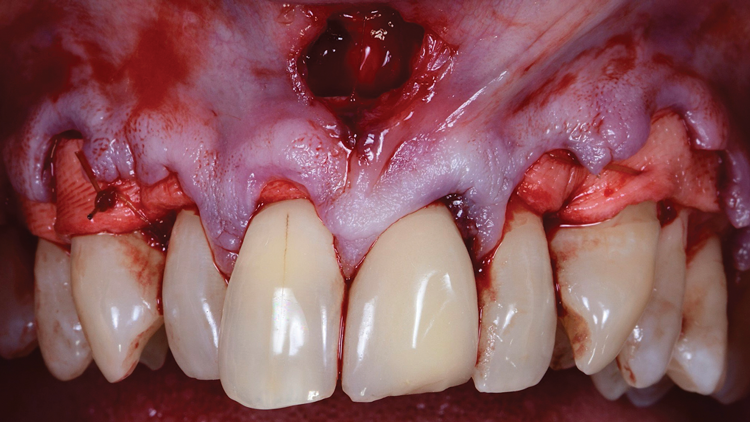

Another flap design, tunnel flaps,16 are very popular in esthetically demanding areas such as the upper anterior teeth due to their lack of papillae reflection, which preserves both the blood supply as well as the papillary height (Figure 2). Only sulcular incisions are utilized, and the graft is introduced over the root surfaces via a sulcular access. The disadvantages of tunnel flaps include increased technique sensitivity and the potential for complications, such as flap perforation, inadequate flap release to allow enough room for the graft materials, and passive closure over the gingival recessions. In addition, access to root surfaces may be a challenge because no flap is reflected to permit visualization.

(2.) Example of a tunnel flap over the maxillary left central incisor being used to place a soft-tissue graft. They are very popular in esthetically demanding areas, such as the upper anterior teeth, because they do not involve papillae reflection.

Figure 2